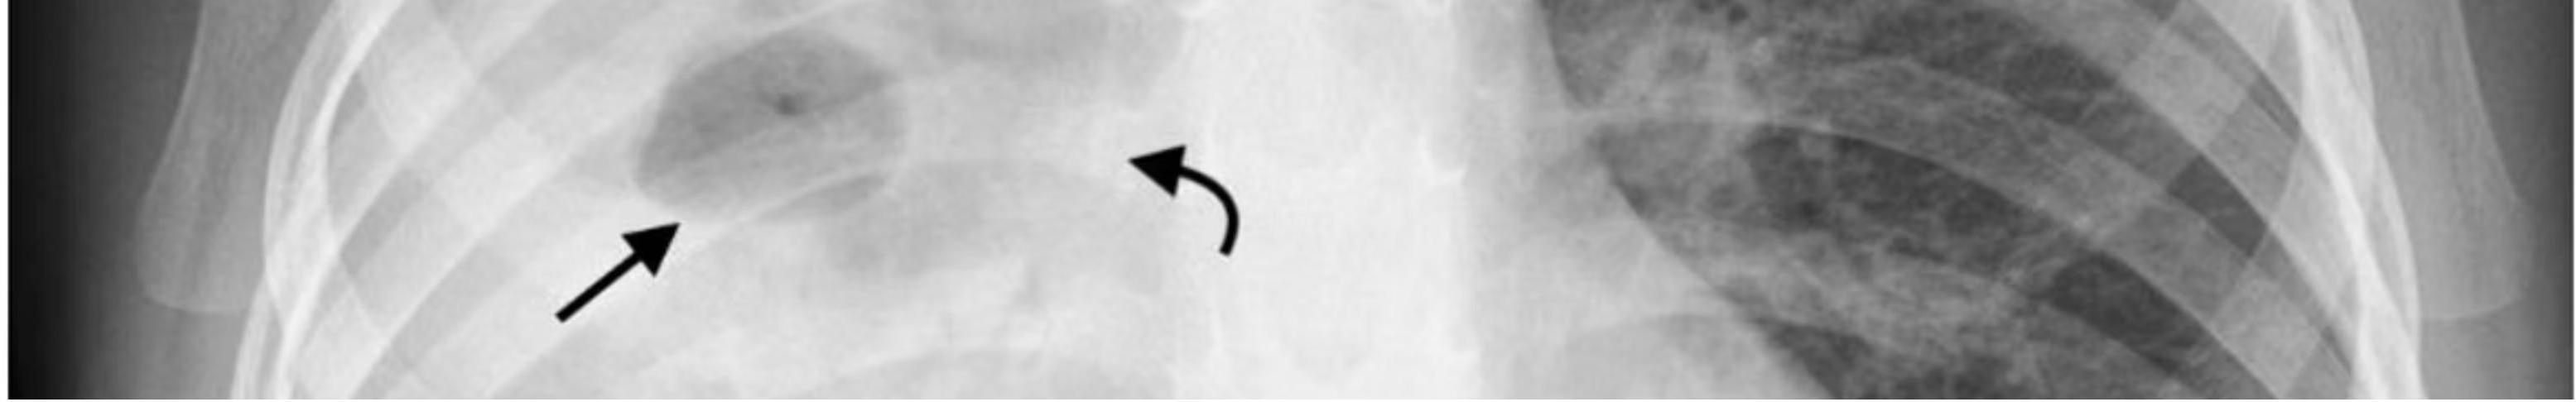

3. Lymph Node Involvement (The Primary Complex)

The local host response may fail to contain inhaled M. tuberculosis, allowing spread via the lymphatic system to regional lymph nodes. The lung lesion plus the lymph node constitutes the ‘Ghon (or primary) complex’.

- Enlarged peribronchial lymph nodes may cause bronchial compression/obstruction and distal atelectasis, leading to collapse and consolidation of affected lung segments.

Most cases of primary tuberculosis heal at this stage, leaving only a small fibrocalcific scar in the lung and mediastinum (Ranke complex), sometimes visible on chest x-ray.

(b) Chest X-ray of pulmonary TB. There is marked left hilar lymphadenopathy.